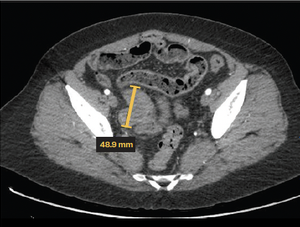

Granulosa cell tumors exhibit late recurrence and rare hepatic metastasis, emphasizing the need for lifelong surveillance in affected patients.